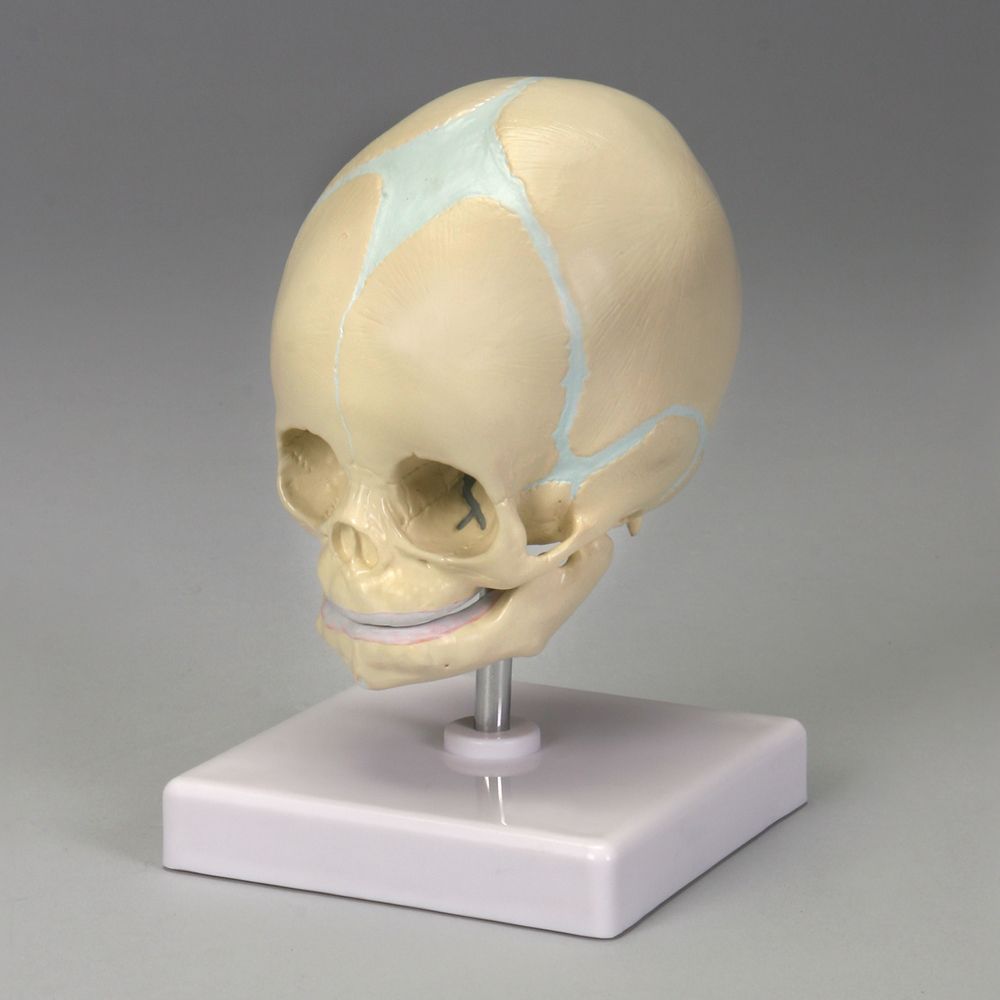

www.turbosquid.comBuy Human Infant Skull Model, Life Sized Fetus Skull, Anatomy Baby

www.turbosquid.comBuy Human Infant Skull Model, Life Sized Fetus Skull, Anatomy Baby

store.toolband.comAltay Fetal Skull | Carolina Biological Supply

store.toolband.comAltay Fetal Skull | Carolina Biological Supply

www.carolina.comskull fetal altay carolina

www.carolina.comskull fetal altay carolina

www.shop.musictoday.comHuman Fetal Skulls Set Of 12 - Bone Clones - Osteological Reproductions

www.shop.musictoday.comHuman Fetal Skulls Set Of 12 - Bone Clones - Osteological Reproductions